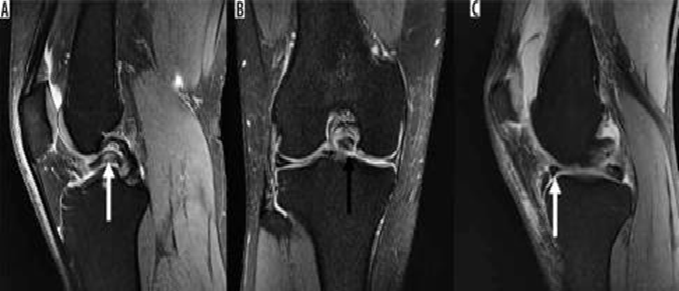

Hình 3. Hình ảnh cộng hưởng từ có trọng số mật độ proton sagital có sụn chêm bên dạng đĩa với tín hiệu tăng trong sụn.

Hình 4. Rách sụn chêm, nang sụn chêm. Hình ảnh coronal xóa mỡ có u nang nhỏ (mũi tên đen) tiếp giáp với thân của sụn chêm bên có vết rách liên quan đến sụn chêm (mũi tên trắng)

Hình 5. Vết rách ngang sụn với mảnh di lệch. Hình ảnh pd xóa mỡ với vết rách sụn chêm giữa và mảnh di lệch (mũi tên) nằm giữa dây chằng chéo giữa và mâm chày giữa.